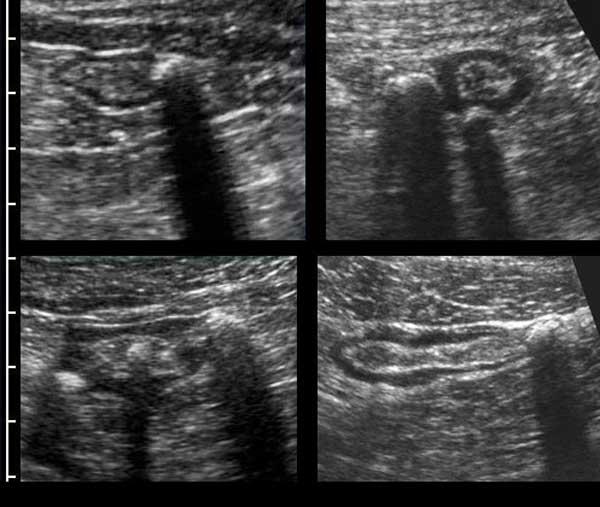

Appendix

Một kỹ thuật viên siêu âm có kinh nghiệm có thể xác định toàn bộ ruột thừa bình thường – bao gồm cả đầu tận cùng bịt kín – ở khoảng 30% bệnh nhân người lớn và 80% bệnh nhân trẻ em.

Siêu âm toàn bộ ruột thừa bình thường, loại trừ viêm ruột thừa.

Ruột thừa bình thường có các lớp tương tự như thành ruột bình thường. Ở người phụ nữ trẻ này, cả năm lớp đều có thể nhìn thấy bao gồm lớp thanh mạc, nhờ có một lượng nhỏ dịch trong ổ phúc mạc.

Lưu ý lòng ống rỗng và mạc treo ruột thừa tăng âm hình tam giác bình thường.

Để nén ruột thừa, cần có một nền cứng chắc bên dưới như động mạch chậu, cơ thắt lưng chậu hoặc thân đốt sống.

Ruột thừa bình thường (đầu mũi tên) được phân biệt với ruột non dựa vào vị trí, kích thước, sự vắng mặt của nhu động ruột, sự gắn kết với cực manh tràng (c.p.) và đầu tận cùng bịt kín (mũi tên).

Đầu mù của ruột thừa bình thường được thể hiện rõ ràng bằng cách sử dụng “kẹp mini”.